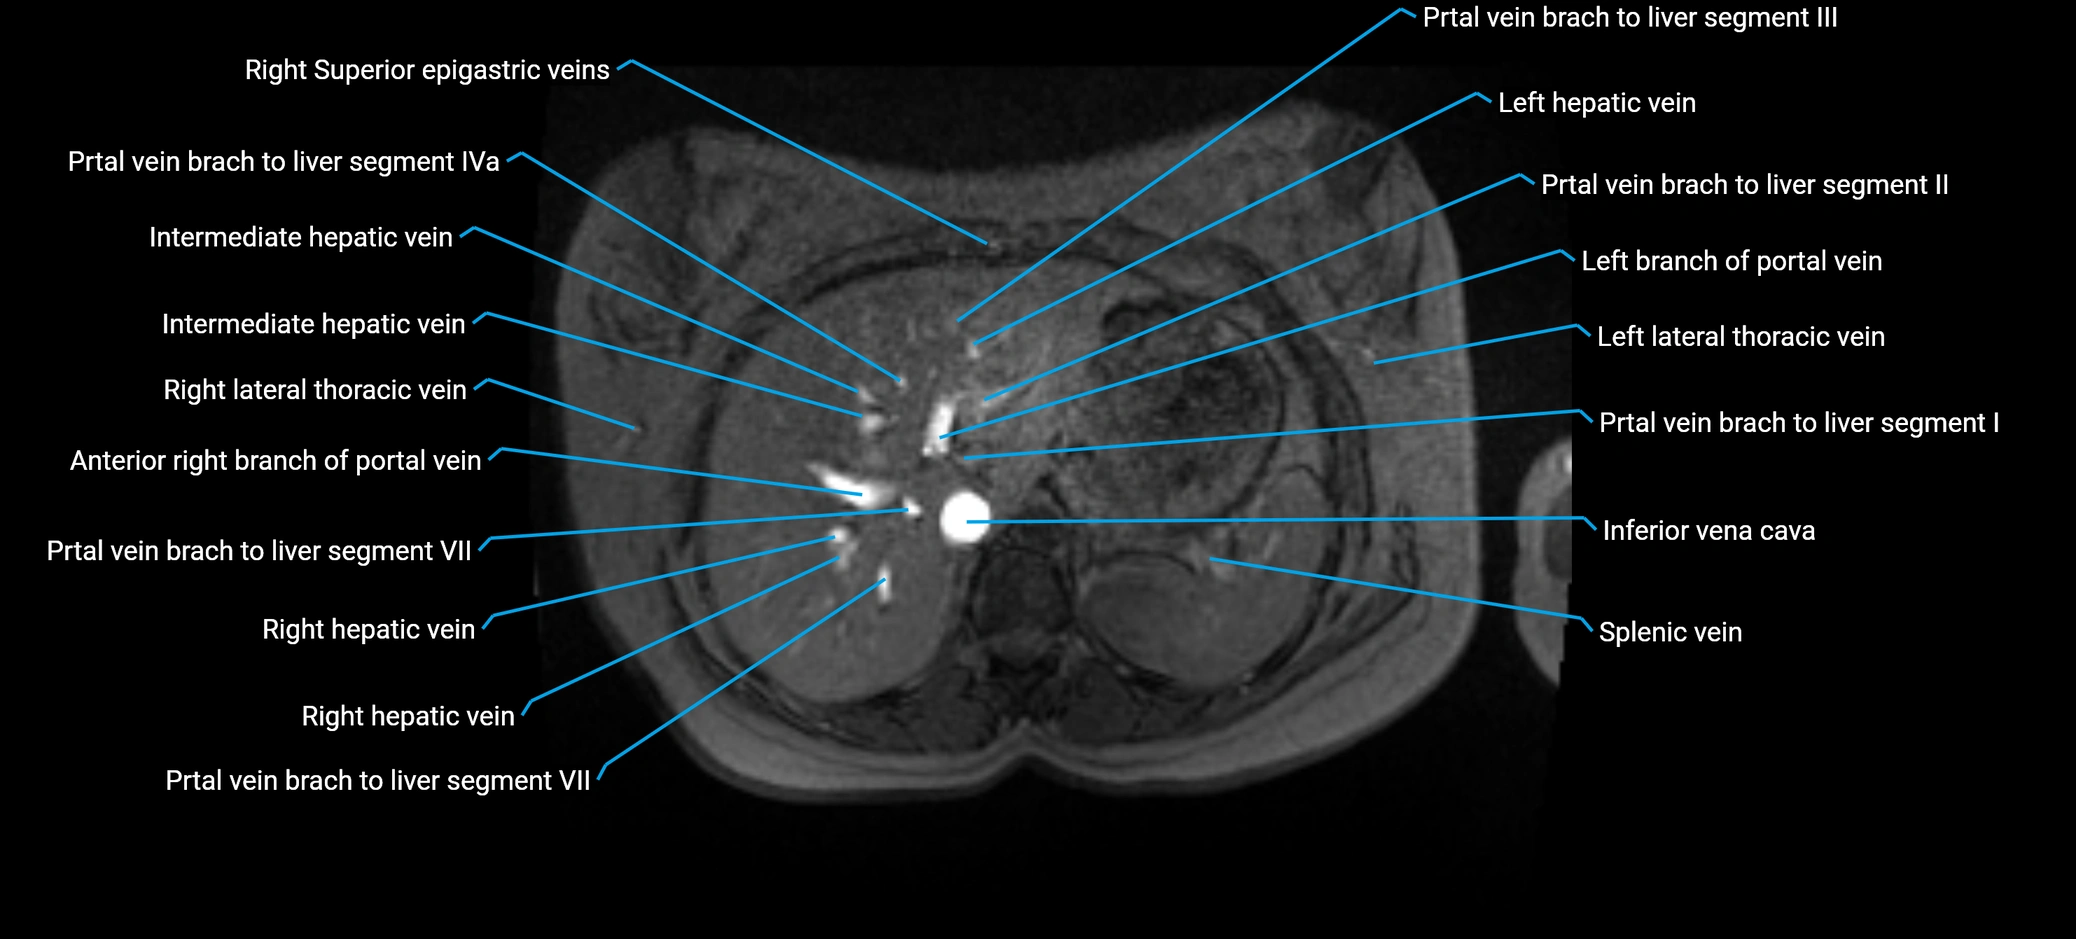

The anterior right branch of the portal vein is a major intrahepatic division of the right portal vein. After the main portal vein bifurcates into right and left branches, the right portal vein divides into anterior and posterior segmental branches.

The anterior right branch supplies the anterolateral liver segments (Segment V) and anteromedial liver segments (Segment VIII) within the right hepatic lobe. It operates as a key vascular route delivering nutrient-rich portal venous blood to the central and superior right liver.

This segmental vasculature is of major importance in hepatic surgery, embolization, segmental resection, transplantation, and imaging-based liver segmentation.

MRV TOF (Time-of-Flight MR Venography):

• Appears as a bright, high-signal vascular channel representing flowing blood

• Clearly shows branching pattern of right portal vein into anterior and posterior branches

• Best in coronal or axial reconstructions for segmental mapping

• No need for contrast, relies on flow-related enhancement